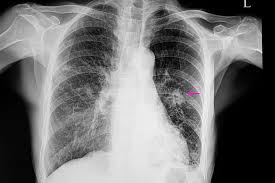

Kemik ağrısı (tipik olarak arkada veya kalçada) Beyin veya omuriliğe yayıldığında, baş ağrısı, halsizlik, uyuşukluk, baş dönmesi, denge sorunları ve nöbetler gibi belirtiler oluşabilir. Kanser karaciğere yayıldığında sarılık ve ciltte sararma meydana gelir. Kanser deriye veya lenf noduna yayıldığında vücudun yüzeyine yakın topaklar oluşur. Tanı Nasıl Konulur? Düz akciğer röntgenleri ile akciğerde kitle görülen hastalara,öncelikle bilgisayarlı tomografi çekilir.Elde edilen üç boyutlu görüntü ile kitleye nasıl ulaşılabileceğine karar verilir.Hastadan ya tomografi rehberliğinde ya da bronkoskopi dediğimiz ince bükülebilir bir tüple akciğerine ulaşılarak iğneyle parça alınır.Bu işleme biyopsi adı verilir. Gerekli görüldüğü takdirde farklı görüntüleme tetkikleri de yapılabilir. Tedavi Her hastanın tedavisi farklılık göstermekte olup, tedavi kararında hastalığın yeri, evresi, hastanın yaşı ve diğer sağlık sorunları gibi birden fazla faktör etkilidir. Multidisipliner bir çalışma gerektiren bu tedaviler ;cerrahi, hedefe yönelik tedaviler radyoterapi, kemoterapi gibi farklı seçenekleri içermektedir. Akciğer Kanseri Türleri Nelerdir? Çoğu akciğer kanseri bronşları saran zardan (plevra) başlar. Bronşlar trakea dediğimiz soluk borumuzdan dallanan hava geçiş yollarıdır. Akciğer kanseri, bronşları saran zarın altındaki bezlerde, sıklıkla akciğerlerin dışında oluşur. Bu tümörler, her biri farklı şekillerde büyüyen ve yayılan küçük hücreli veya küçük hücreli olmayan akciğer kanseri olmak üzere iki ana tipten oluşur.

Küçük hücreli olmayan akciğer kanseri çok daha yaygındır ve genellikle küçük hücreli akciğer kanserinden daha yavaş büyür ve yayılır. Küçük hücreli akciğer kanseri, tüm akciğer kanserlerinin yaklaşık yüzde 15’ini oluşturur. Bu tip akciğer kanseri hızla büyür, tanı konulurken ilerleyip vücudun diğer bölgelerine hızla yayılabilir. Akciğer Kanseri Belirtileri Nelerdir? Akciğer kanseri belirtileri ve semptomları genellikle hastalık ilerleyince ortaya çıkar. Bununla birlikte, bazı insanlarda görülen erken belirtiler şunlardır: · İyileşmeyen öksürük, · Ses kısıklığı, · Balgam veya öksürme ile atılan kanlı balgam, · Güçsüzlük, · Hırıltı, · Tekrarlayan veya iyileşmeyen enfeksiyonlar, · Öksürük veya kahkaha ile kötüleşen göğüs ağrısı. İlerlemiş akciğer kanseri semptomları arasında öksürük, nefes darlığı, göğüs ağrısı, yorgunluk ve/veya istenmeyen kilo kaybı bulunur. Kanser başka yerlere yayılırsa ortaya çıkabilecek belirti ve semptomlar arasında kemik ağrısı, baş ağrısı, kas güçsüzlüğü ve/veya göz kapağı sarkması bulunurtr Akciğer Kanseri Nasıl Teşhis Edilir ve Yönetilir? Genellikle, bir hastanın akciğer kanseri olabileceği şüphesi, göğüs görüntülemede anormal bir bulgu olunca veya hastalık öksürük, nefes darlığı, göğüs ağrısı, yorgunluk ve/veya kilo kaybı gibi semptomlara neden olacak kadar ilerlediğinde oluşur. Tanı biyopsi veya şüpheli kitleden hücre veya dokuların çıkarılmasını gerektirir. Biyopsiler soluk borusundan (bronkoskopi olarak adlandırılır) bir kamerayla veya deri yoluyla akciğer tümörüne sokulan bir iğneden yapılabilir. Bu yaklaşımlar başarılı olmazsa, yeterli tanı için ameliyat gerekebilir. Biyopsi, kanser olup olmadığını ve hangi tip akciğer kanseri olduğunu belirlemede önemlidir. Akciğer kanseri taraması Akciğer kanseri taraması, hastalığı erken evrede yakalayabilmek için kanser belirtisi olmayan akciğer kanseri geliştirme riski yüksek olan sağlıklı bir bireylere düşük doz göğüs BT görüntülemesi yapılmasını kapsar. Bu taramanın, yüksek kalitede yapıldığında kabul edilebilir oranda akciğer kanserinden ölen insan sayısını azalttığı bulunmuştur.Not:Doktorunuza danışın.